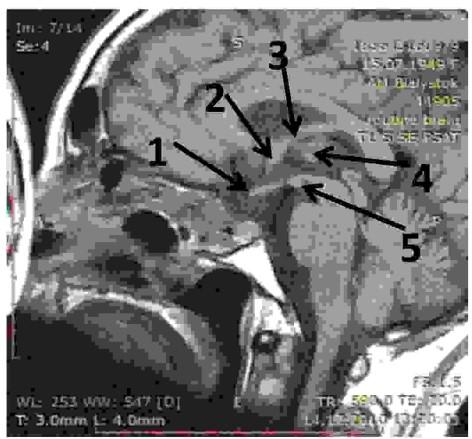

Rycina przedstawia skan rezonansu magnetycznego w płaszczyźnie strzałkowej, nieco bocznie od linii pośrodkowej. Wskaźnik prawidłowo zaznacza położenie spoidła przedniego?